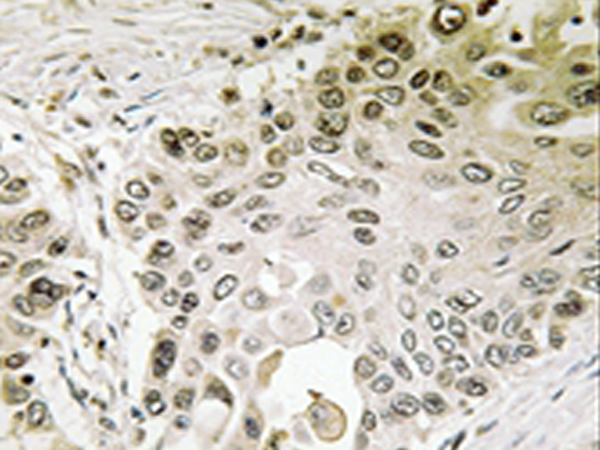

IHC |

IHC positive control: |

Human lung carcinoma tissue |

IHC Recommend dilution: |

50-100 |